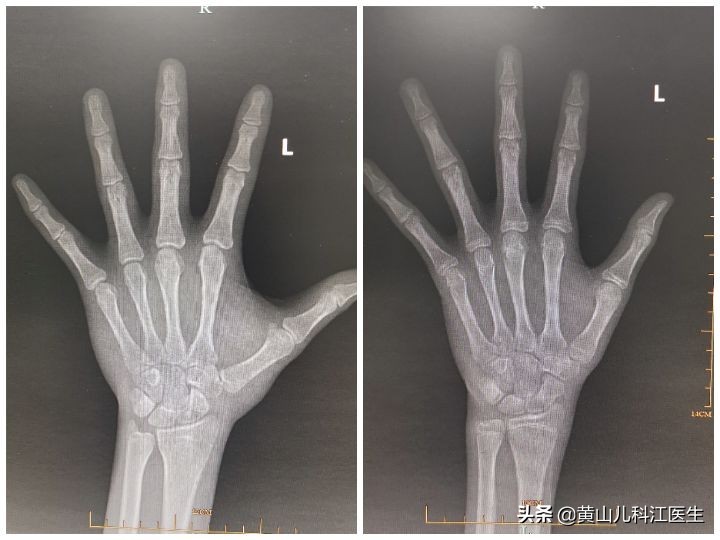

1、人体身高的增长取决于长骨的增长速度和成熟度(骨龄超前/性早熟),适宜的运动可以促进骨骼血液循环和增进骨的代谢。